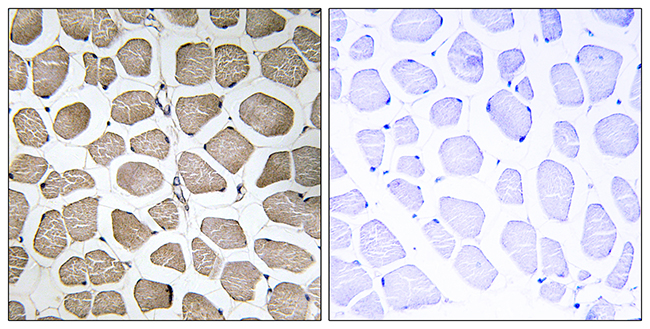

Anti-MEF2C AntibodyA98862

ApplicationsELISA, ImmunoHistoChemistry

ReactivityHuman, Mouse

- SizePrice